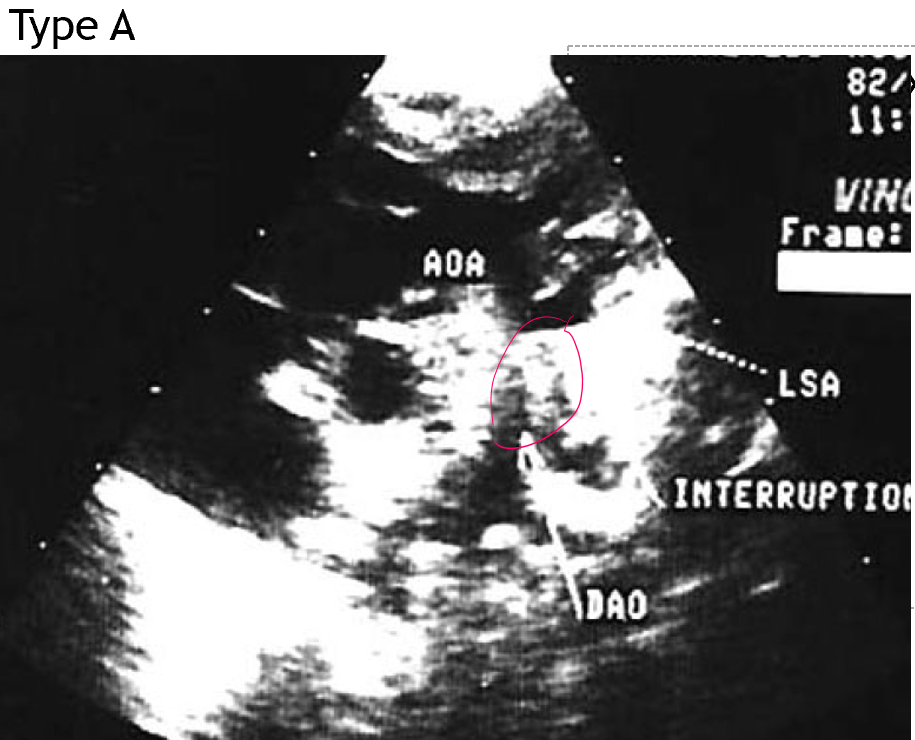

what is interrupted ao arch type A?

interruption found at isthmus

origin of the subclavian artery and the insertion of the ductus arteriosus

distal to left subclavian artery

type A IAA is associated with

50% VSD

how can type A IAA present clinically?

difference of BP of upper and lower extremities